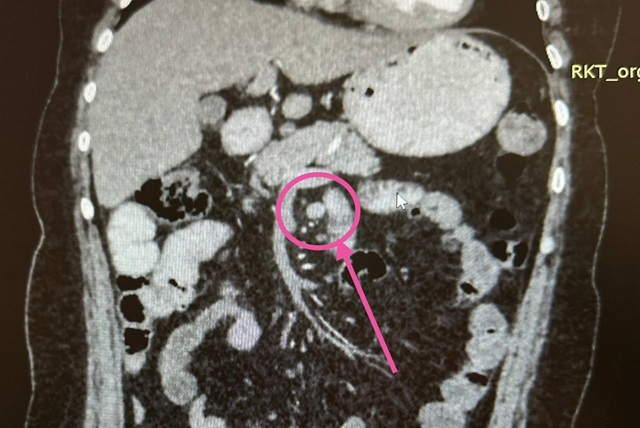

Почти две недели женщина проходила различные исследования, и в конце-концов в крючке поджелудочной железы рентгенологи обнаружили микроскопическую опухоль. При помощи эндокринологов врачи поставили диагноз — гастринома.

Эта редкая опухоль приводит к развитию язв вследствие большой выработки гастрина — гормона, стимулирующего выработку соляной кислоты в избытке, объяснили врачи.

12 ноября пациентку прооперировали. Она очнулась в реанимации спустя четыре часа, и узнала, что врачи во время операции нашли и удалили вторую такую же опухоль, но в двенадцатиперстной кишке. На ФГДС и КТ вторую опухоль было не видно, поэтому нашли ее при прощупывании пальцами.